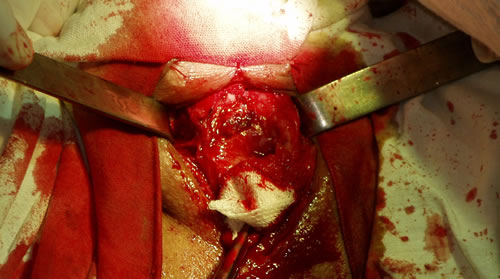

Выделение дистальной части уретры из рубцовых

тканей проксимальнее рубцового сужения уретры, удаление

рубцовых тканей

Выделение из рубцовых тканей проксимальной части уретры

Виден "кратер" проксимальной уретры